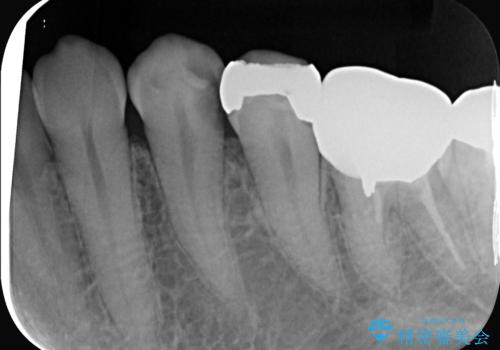

- 左下4番の奥歯に、歯肉の下まで進行した深い虫歯を認め来院されました。通常であれば神経を抜く必要があるほど深い虫歯でしたが、患者様の歯をできる限り保存するため、歯の神経を抜かずに残すことを目指す治療計画を立案。歯肉の下にある虫歯を適切に治療するため、歯周外科処置で歯肉のラインを調整した上で、精密なセラミッククラウンで修復することになりました。

まず、虫歯を徹底的に除去するために、歯周外科処置で歯肉のラインを調整し、治療部位を露出させました。その後、神経に近接した深い虫歯を慎重に除去。神経の保護処置を施し、歯の神経を抜くことなく保存することができました。型取りから、患者様の歯の色や形に合わせたオーダーメイドのセラミッククラウンを作製。最終的に、精度の高いクラウンを装着し、咬み合わせを細かく調整しました。これにより、神経を温存しながら、虫歯の再発を防ぎ、快適な咬み心地を取り戻していただけました。